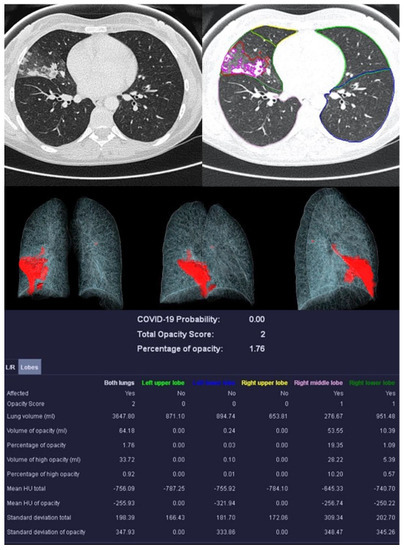

Figure 5.

Sample examination of a healthy 67-year-old patient. Only global bronchial wall thickening and mucus impactions can be seen.